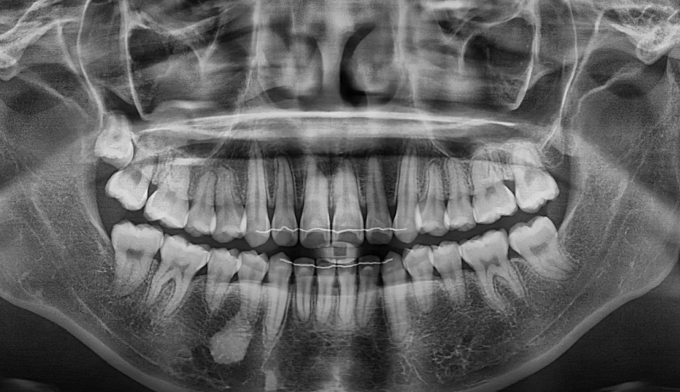

비교적 6개월이라는 짧은 기간안에 교정이 마무리되었습니다.

처음부터 무리하게 교정치료를 들어가지 않은것이 핵심입니다.